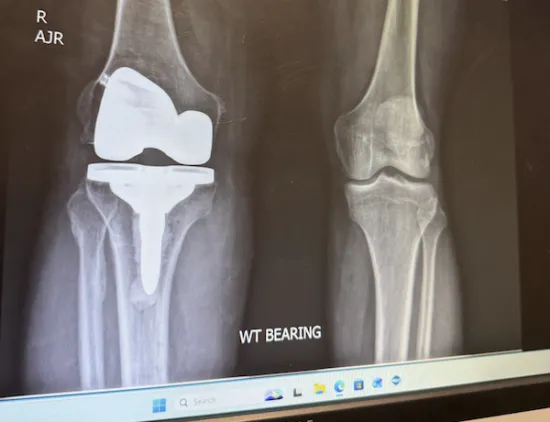

Knee Replacement

My Comeback Story

Dr. Dirk Dolbeare and the physical therapy staff were knowledgeable, caring, and talented. After total knee replacement in April of 2024, I worked diligently with the PT team to recover. It took…

Rod Extraction and Knee Replacement

Great experience with Dr. Erik Bowman

I had a rod extract from my right leg Tibia and my knee replaced. I was playing pickleball nine weeks later. I didn’t think I would be able to do that for at least six months. The surgery went…

Total Knee Replacement

I had a Tibia Plateau fracture in my left knee in 2003 with plates and pins, so I was well due for TKR by the time I went to see Dr. Brian Blackwood in Oct. 2024. I was back to doing CrossFit at 4…

Total Knee Replacement (Left)

Years of Use

My knees have been in rough shape for several years, due to damage from running, weight training, and osteoarthritis. I stopped running due to bone-on-bone pain, and workouts were becoming more…

Full knee replacement

Should have done this sooner!

After being bone on bone for 14 years, it was time to get a new part. After consulting with Dr. Seng and then Dr. Blackwood, it was time. I couldn’t be happier with the procedure, the physical…